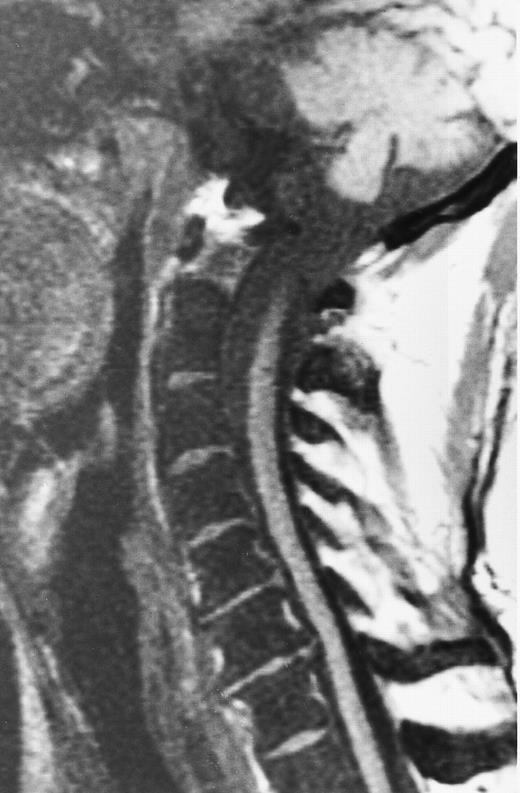

A 51-year-old man with chronic myeloid leukemia and hemosiderosis of the bone marrow due to multiple prior blood transfusions. Sagittal T1-weighted (500/10, TR/TE) MR image of the cervical spine shows marked hypointensity of the bone marrow. Note that the intervertebral discs are hyperintense to the abnormal marrow.